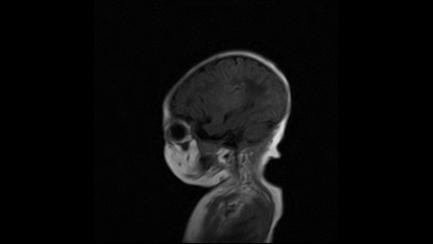

标题: PED3413:患儿女6天体检

缺血缺氧性脑病

6天为新生儿,髓鞘发育正常;左侧颞顶叶蛛网膜下腔增宽,请结合临床。

1。缺血缺氧性脑病2。左侧颞顶叶外部性脑积水,可观察

半卵圆中心上方层上可见对和乐大脑皮质t1高信号,考虑有hie可能,不知有何症状,建议加做dwi及复查

符合缺氧缺血性脑病影像表现。